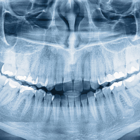

Disponemos de la aparatología adecuada para conocer el estado exacto de tu salud dental.